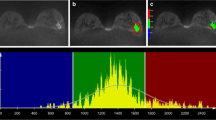

Eighty-six consecutive women with 86 DCIS lesions diagnosed by biopsy underwent UF-MRI including pre- and 18 post-contrast ultrafast scans (temporal resolution of 3 s/phase). The last phase of UF-MRI was used to perform 3D segmentation. The time point at 6 s after the aorta started to enhance was used to obtain subtracted images. From the 3D segmentation and subtracted images, enhancement, shape, and texture features were calculated and compared between low- and non-low-grade or upgrade DCIS lesions using univariate analysis. Feature selection by least absolute shrinkage and selection operator (LASSO) algorithm and k-fold cross-validation were performed to evaluate the diagnostic performance.

Mori N, Abe H, Mugikura S, et al. Ultrafast dynamic CONTRAST-ENHANCED BREAST MRI: kinetic curve assessment using empirical mathematical model validated with histological microvessel density. Acad Radiol. 2019;26:e141–9.

Mori N, Pineda FD, Tsuchiya K, et al. Fast temporal resolution dynamic contrast-enhanced MRI: histogram analysis versus visual analysis for differentiating benign and malignant breast lesions. Am J Roentgenol. 2018;211:933–9.